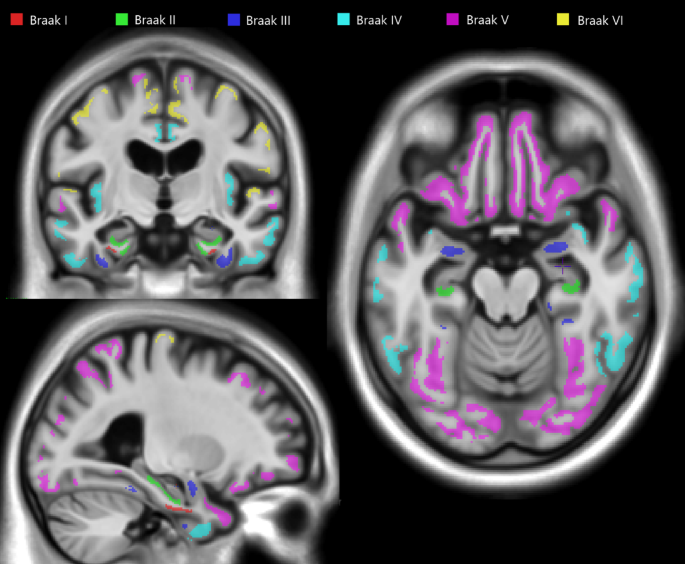

We obtained a global amyloid-PET load using the average SUVR from a region of interest (ROI) encompassing the precuneus, prefrontal, orbitofrontal, parietal, temporal, anterior, and posterior cingulate cortices33. An amyloid-PET uptake ≥ 1.55 was considered amyloid-β-positive (A+)34. Tau-PET SUVRs were obtained from updated ROIs corresponding to Braak stages I through VI (Fig. 129,35,36). For each of these six ROIs, a threshold was established based on 2.5 standard deviations above the mean of a subgroup in the TRIAD cohort aged 18–25 years34,36. Braak stages were then established based on the highest Braak ROI threshold surpassed, provided that all previous Braak ROI thresholds were also surpassed. Tau-PET uptake was also obtained from the MTL ROIs. These were extracted from the non-smoothed PET images aligned with the participant’s original T1w MRI.